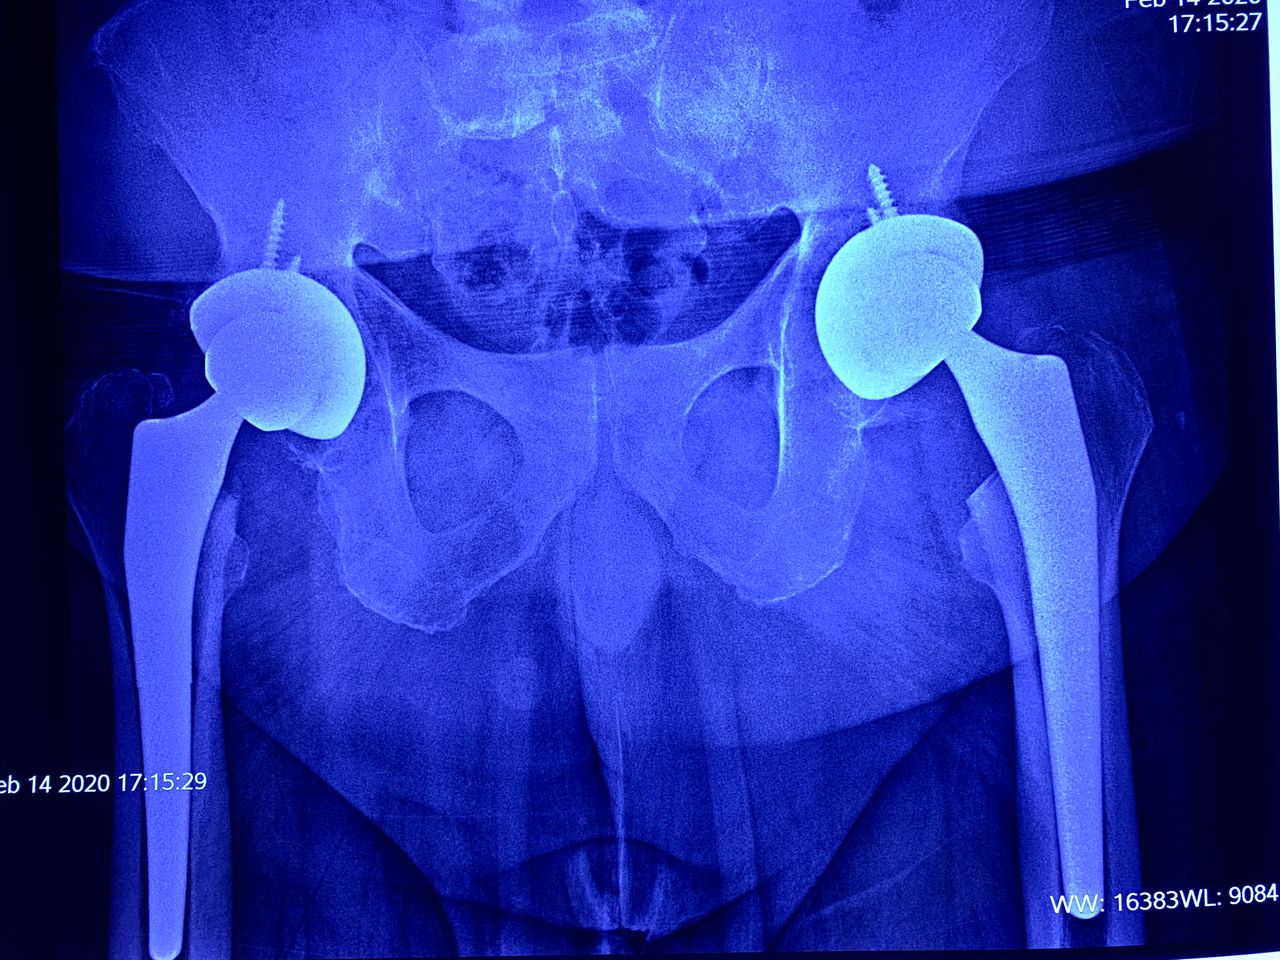

El Dr. Luis Hernández Romero cuenta con adiestramiento especial en cirugía de Columna, artroscopia y reemplazos articulares ( Prótesis de rodilla y cadera ), así como Cirugía de Reconstrucción Articular y Cirugía de Hombro con uso de técnicas de mínima invasión realizados en Barcelona, España. Congresista activo en los diferentes foros de Cirugía Articular nacionales e internacionales acrecentando su acervo por la capacitación médica continúa en México, Estados Unidos, España, Argentina   y  Corea del Sur. Pionero en la reconstrucción de ligamento cruzado anterior con aloinjerto ( tejido de banco de hueso y tendones de cadáver) vía artroscópica en la ciudad. Colaborador incondicional de sus colegas Traumatólogos, ha sido invitado por Ortopedistas reconocidos a participar activamente en cirugías de rodilla en los diferentes hospitales de la localidad. Actualmente el Dr. Luis Hernández  es el Jefe de Traumatología del Hospital México Americano y Presidente del staff de Médicos del Hospital México Americano, hospital que lo incorporó en su Staff fundador desde 2012, Ortopedista encargado de formar el Departamento de Traumatología y solicitar toda la tecnología necesaria y de vanguardia para las cirugías que requiere la especialidad, destacado miembro fundador del servicio participa como experto en cirugía de prótesis de rodilla, realizando desde 2005  cirugías articulares de rodilla al alcance de la comunidad neolaredense sin necesidad de trasladarlos a otra ciudad, siendo el Traumatólogo con Especialidad en rodilla con más procedimientos practicados año con año en todos los Hospitales de Nuevo Laredo avalado por la bitácora de programación de cirugías. NOMBRADO DESDE   OCTUBRE  DE  2015  JEFE  DE  ORTOPEDIA  Y  TRAUMATOLOGIA  DEL  HOSPITAL MEXICO  AMERICANO  Y  DESDE   2017  COMO  PRESIDENTE  DEL STAFF  MEDICO  DEL  MISMO HOSPITAL.

• Reemplazo articular de cadera